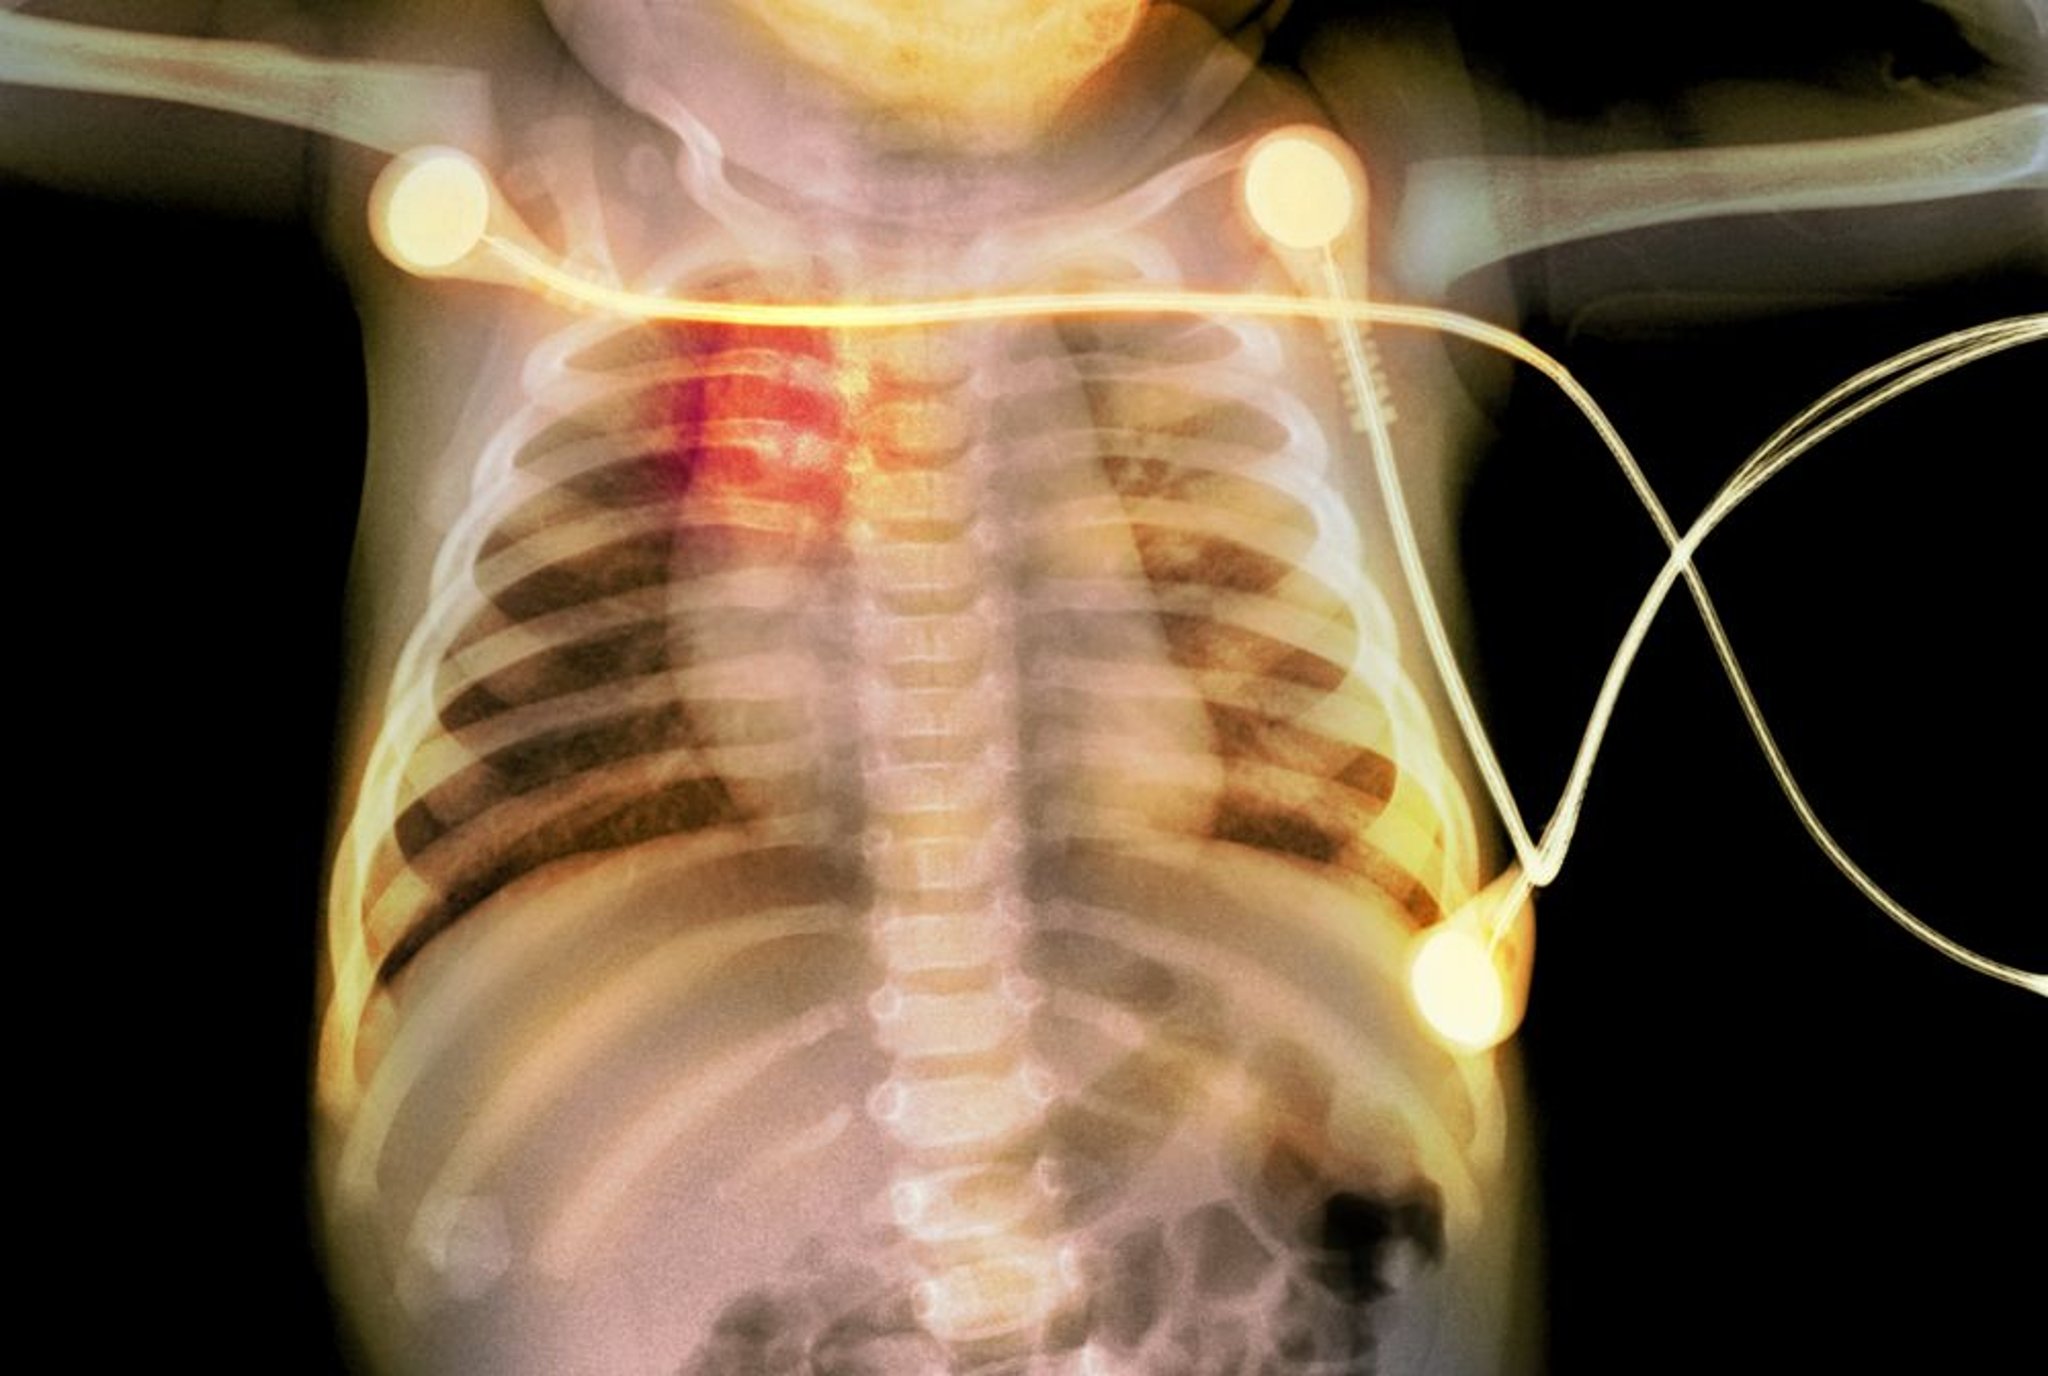

Fracturas costales en un bebé

Esta radiografía muestra fracturas costales (resaltadas en rojo) en un bebé que sugieren maltrato infantil.

PHOTOSTOCK-ISRAEL/SCIENCE PHOTO LIBRARY